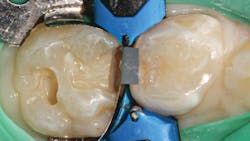

A selective-etch technique with 35% phosphoric acid is used to achieve the highest possible bond strengths.6,7 The etchant is washed and the tooth is dried without desiccating it. A universal bonding agent (Futurabond U, Voco) is rubbed onto the tooth surface for 20 seconds (figure 3), and thenThis is a modified snowplow technique, in which the flowable base layer is light cured in combination with placement of 4 mm of the restorative material.8,9 This allows the flowable to extrude up to the occlusal surface and down to the gingival margins, filling any voids.